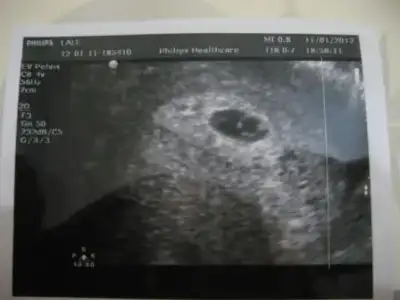

dün doktora gittim kızlar...işte bu benimki :emir_bebek:... keseyi gördüm ve kalp atışları duydum :nazar::nazar:.... doktorda tek taşa benziyor dedi :21:

Eki Görüntüle 326688